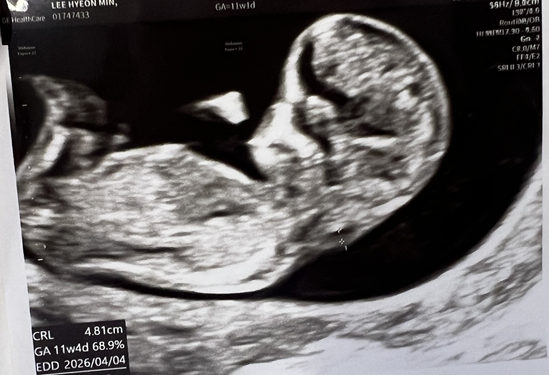

안녕하세요~~! 오늘 11주차 초음파 보고왔는데 각도법 질문드립니다 ㅎㅎ 아들일까요 딸일까요??!